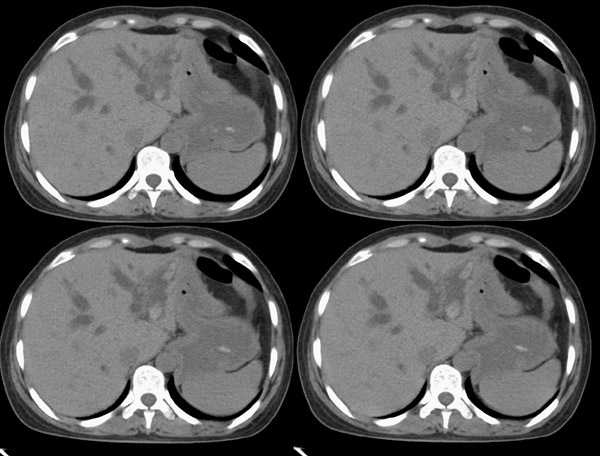

f42y近半月来无明显诱因出现右上腹疼痛之主诉就诊。疼痛多于饭后半小时发作,为持续性隐疼,呈阵发性、刀割样、钻顶样疼痛加剧,且向右肩背部放射,伴恶心、出汗、呕吐,呕吐内容物为胃内容物,无呕血,时有返酸、呃逆、烧心感,无腹胀、腹泻及黑便。时有发冷、发热(但体温不高);呕吐后腹疼稍有缓解,在当地诊所按“胃炎”对症治疗10天,效果不佳。血常规为:白细胞:9、8*109,中性64%,血红蛋白为151g/l,血小板为167*107。 既往有胆道蛔虫病史30余年,曾有呕虫史,否认肝炎及肺结核、溃疡病史。无外伤、手术及药物过敏史,陕西丹凤县四坪镇人,未去过疫区。

腹部ct平扫:(5mm层厚)